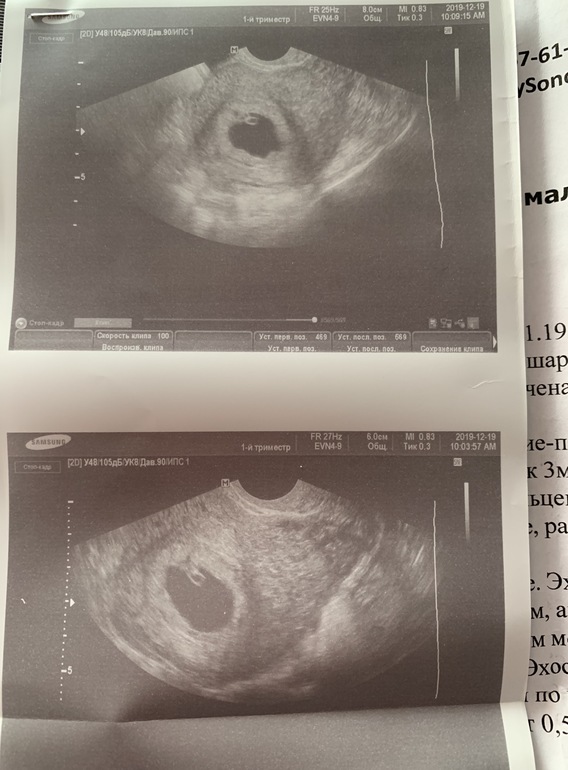

Узи в 6 нед 4 дня (неровные контуры ПЯ)

Вопросы про УЗИ, обследования и анализы: что, где, как, когда?Девочки, привет) в общем, сходила я на узи и подумала, что лучше бы не ходила и спала спокойно 🤦🏽♀️ Пришла на приём, сделали узи: СВД 18 мм, ктр 6 мм, сб +, жт хорошее и все бы отлично , соответсвует сроку... но! Девочки! Плодное яйцо в одной из проекций узи имеет такие неровные контуры,

честно сказать, я такого никогда не видела ! (Фото прилагаю) Они прям очень деформированы, при том в другой проекции - все супер, ровненькое яичко, Г сказала, что такие контуры, тревожный знак, хоть и тонуса нет.... в общем, наблюдение и контроль через неделю (я не планировала так часто на узи ходить!, но и пропустить что-либо опасное не хочется). Девочки, что скажете? У кого так было? Есть Надежда на благополучный исход Б с таким ПЯ?

Моя сказала, что там малюсенькая гематомка есть, но она уже затянулась... на неё она даже внимания не обратила. Только на форму ПЯ. Кстати, по поводу лежать ничего мне не сказала,она просто сказала, что «как будет, так и будет, от нас ничего не зависит».я-то с ней в этом согласна, но лицо она сделала очень печальное ))))

Мне кажется, что локальный тонус есть. Вот оно и помялось немного. Не переживайте все будет хорошо. Врач просто перестраховывается. У меня тоже было разных форм от фасолины до не пойми какой фигуры, все в итоге хорошо.